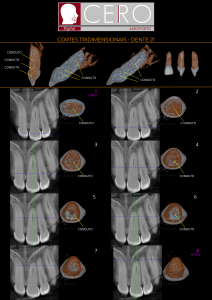

Tomografia Computadorizada

A CERO trabalha com aparelho de última geração para um melhor diagnóstico e detalhes precisos.